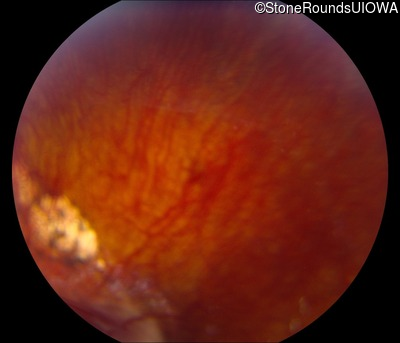

AD Familial Exudative Vitreoretinopathy (IIIE2b)

Age at visit: 23 months

This 23 month old male has had nystagmus since shortly after birth. He was born at term (7lbs 12oz).

AD Familial Exudative Vitreoretinopathy FZD4 Ser228Arg AGC>CGC   AD